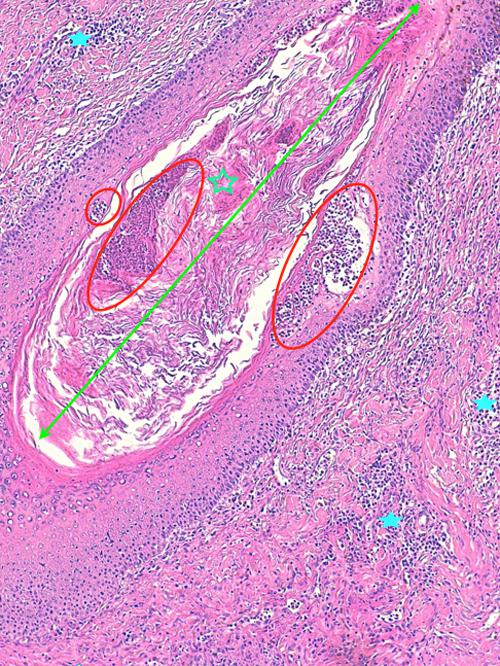

Photo 14 (Hémalun Eosine X 100) peau velue : Dans le derme, les pelotons de

glandes sudorales épitrichiales sont entourés de manchons inflammatoires

associant principalement granulocytes éosinophiles et plasmocytes.

Légendes de la Photo 14 :

- Étoiles rouges : lumière des glandes sudorales apocrines épitrichiales

- Flèches jaunes : infiltrat inflammatoire dermique en manchons péri-sudoraux

Photo 15 (Hémalun Eosine X 40) peau velue : Dans le derme, les pelotons de glandes

sudorales épitrichiales sont entourés de manchons inflammatoires associant principalement

granulocytes éosinophiles et plasmocytes. Leur lumière peut contenir des débris de granulocytes.

Légendes de la Photo 15 :

- Flèche turquoise : granulocyte éosinophile

- Flèche jaune : plasmocyte

- Étoile turquoise pleine : cellule épithéliale glandulaire de la glande sudorale

- Étoile verte : cellule myoépithéliale de la glande sudorale

- Étoile turquoise évidée : cellules inflammatoires dans la paroi de la glande (hidrosadénite)

- Étoile rouge : débris inflammatoires dans la lumière glandulaire (hidrosadénite)

- Rond vert : délimite un peloton sudoral